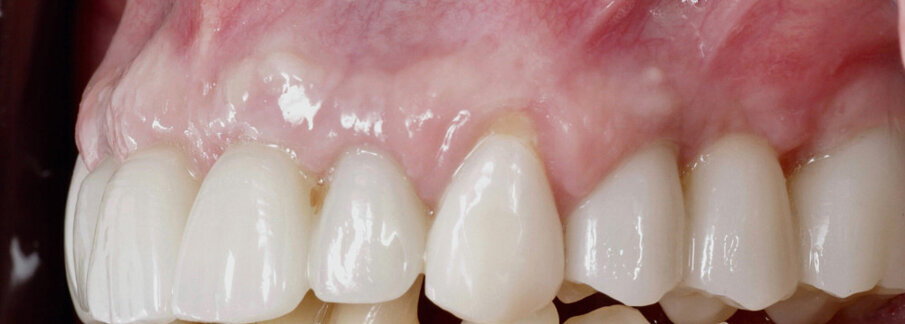

Slika 14. Frontalni prikaz definitivne protetske nadogradnje. Odnosi pokazuju dobru estetiku bez znakova komplikacija mekih tkiva Slika 15. Pogled na definitivni rad s desne strane. Slika 16. Pogled na definitivni rad s lijeve strane. Slika 17. Završna rendgenska slika s definitivnim implanto protetskim radom in situ. Slika 18. Frontalni prikaz definitivnog protetskog rada nakon dvogodišnjeg praćenja. Slika 19. Prikaz definitivnog protetskog rada s lijeve strane nakon dvogodišnjeg praćenja. Slika 20. Prikaz definitivnog protetskog rada s desne strane nakon dvogodišnjeg praćenja.

Definitivni protetski rad napravljen je nakon što je završila faza oseointegracije implantata s tri monolitna mosta od cirkonijevog dioksida (DD CubeX, Dental Direkt) proizvedenih CAD/CAM postupkom. Mostovi su pomoću vijaka pričvršćeni na titanske abutmente (PS TiB, BEGO Implant Systems) (Slike 14–16). Pravilan dosjed protetske nadogradnja se nakon umetanja potvrdio rendgenskom snimkom (Slika 17.). Kontrolni pregled nakon dvije godine u srpnju 2019. pokazao je izvrsno estetsko i kliničko stanje mekog tkiva (Slike 18–20). U području implantata radiografski se nije mogao utvrditi gubitak krestalne kosti (Slika 21.). Oba korijena središnjih sjekutića koji su ostavljeni u alveoli kao ni distobukalni korijen zuba 26 nisu pokazali nikakve znakove periapikalne upale. Pacijentica nije imala nikakvih pritužbi, a oralna higijena značajno se poboljšala tijekom razdoblja praćenja.